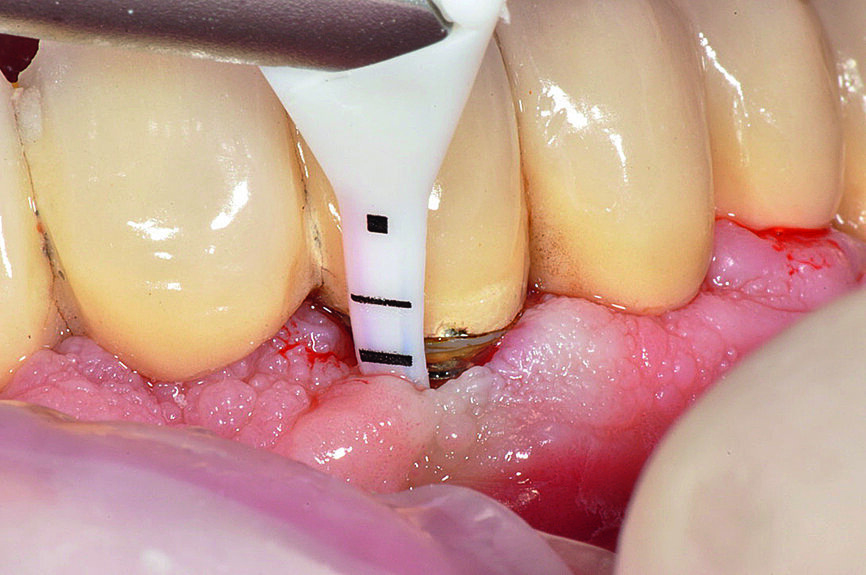

Fig. 8 : Après le scellement

de la prothèse, élimination minutieuse de l‘excès de ciment au moyen d‘un fil dentaire.

Fabrication et assemblage de la prothèse

Le prothésiste dentaire doit travailler en contact direct avec le chirurgien-dentiste afin de créer des espaces permettant un nettoyage confortable et esthétiquement plaisants, adaptés au patient. Après avoir reçu les instructions et les informations de l’hygiéniste bucco-dentaire, les patients doivent être en mesure de nettoyer leurs prothèses quotidiennement et presque sans effort afin de maintenir leur santé orale.13 Un autre facteur important associé aux signes cliniques de péri-implantite est l’excès de ciment.14–17 Pour éviter cet excès, les limites marginales de la restauration doivent être situées au niveau ou au-dessus du bord péri-implantaire de la muqueuse ; sinon l’excès de ciment doit être éliminé.18 En dépit de la littérature internationale démontrant l’intérêt accru que suscite l’excès de ciment considéré comme l’un des facteurs clés dans l’étiopathogénie de la péri-implantite, un protocole standard guidant le clinicien dans cette délicate procédure d’élimination doit encore être mis en place. Selon l’auteur, la technique de scellement demande du temps, de l’attention, le port de loupes binoculaires et de la minutie. C’est pourquoi un protocole précis, dépendant de la composition du ciment, doit être publié (Figs. 7 et 8).